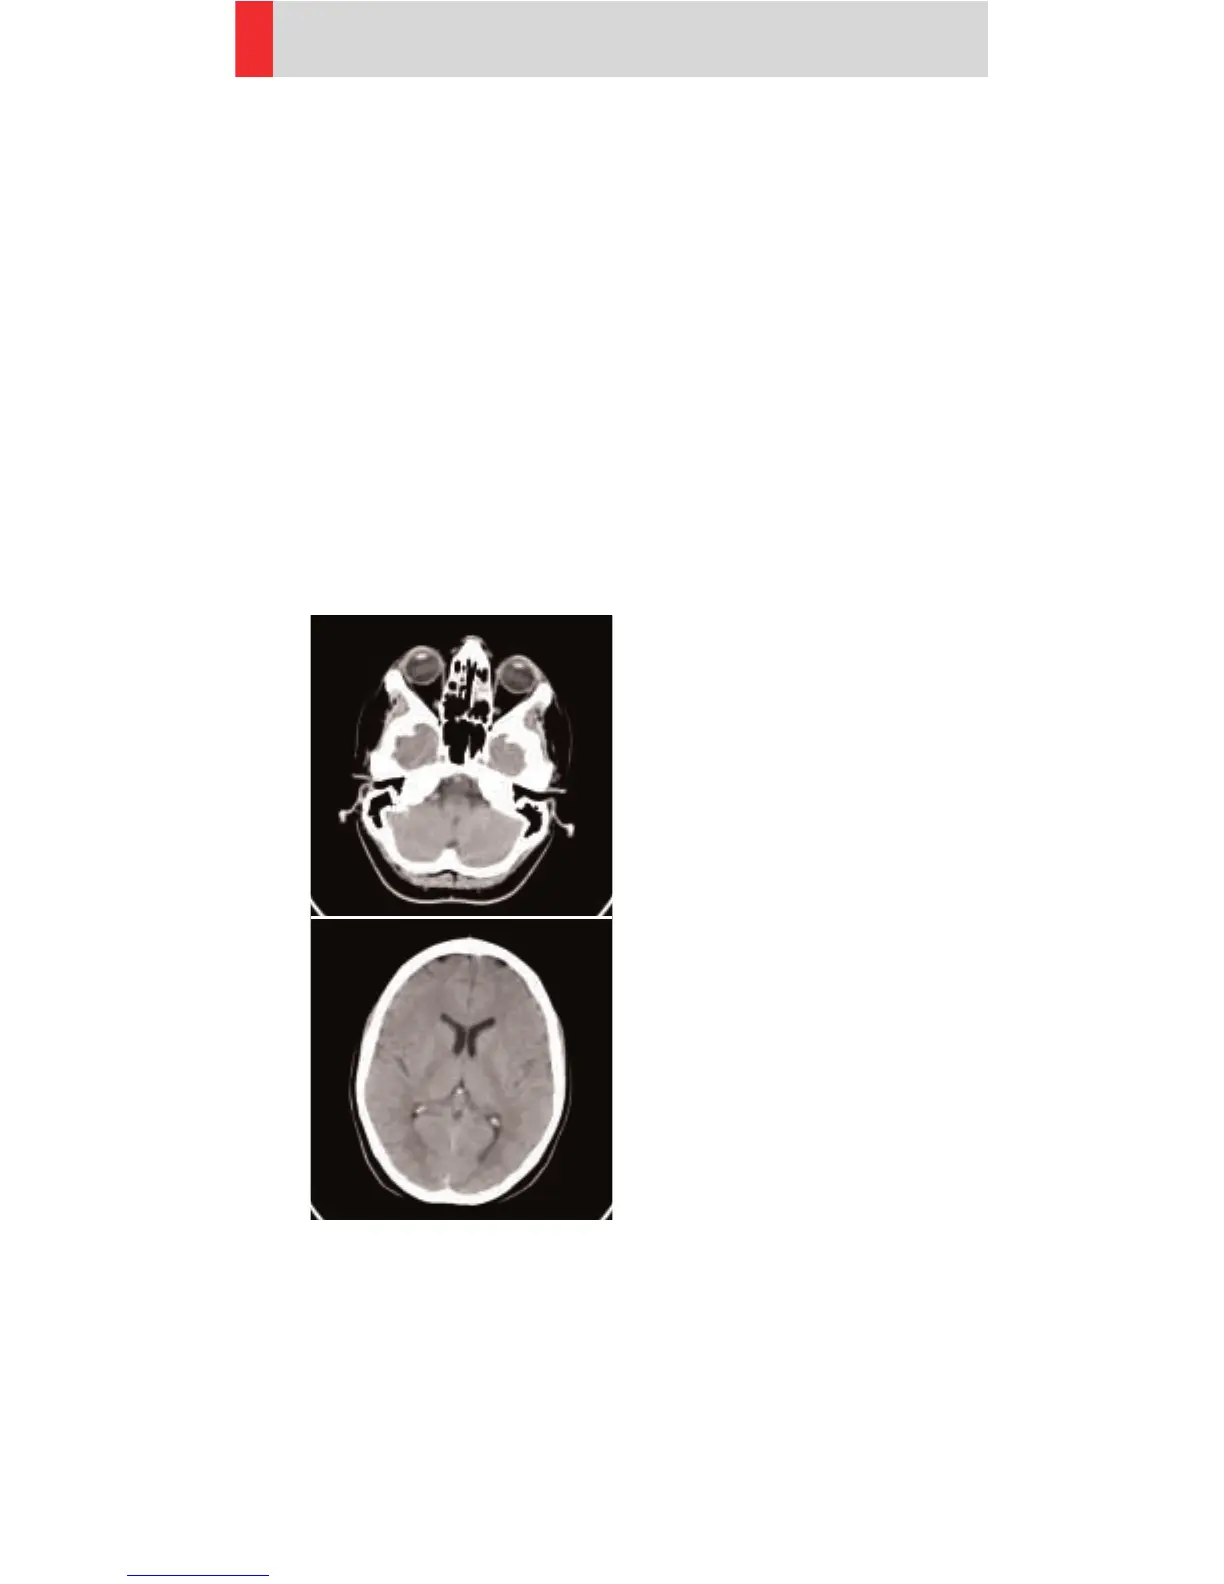

Head

Indications:

Spiral mode for routine head studies, e. g. stroke,

brain tumors, cranial trauma, cerebral atrophy, hydro-

cephalus, and inflammation, etc.

Two ranges are predefined for the base of the skull

and cerebrum.

A range for the base of 40 mm will be covered in

12.0 sec., a range for the cerebrum of 80 mm will be

covered in 12.0 sec.